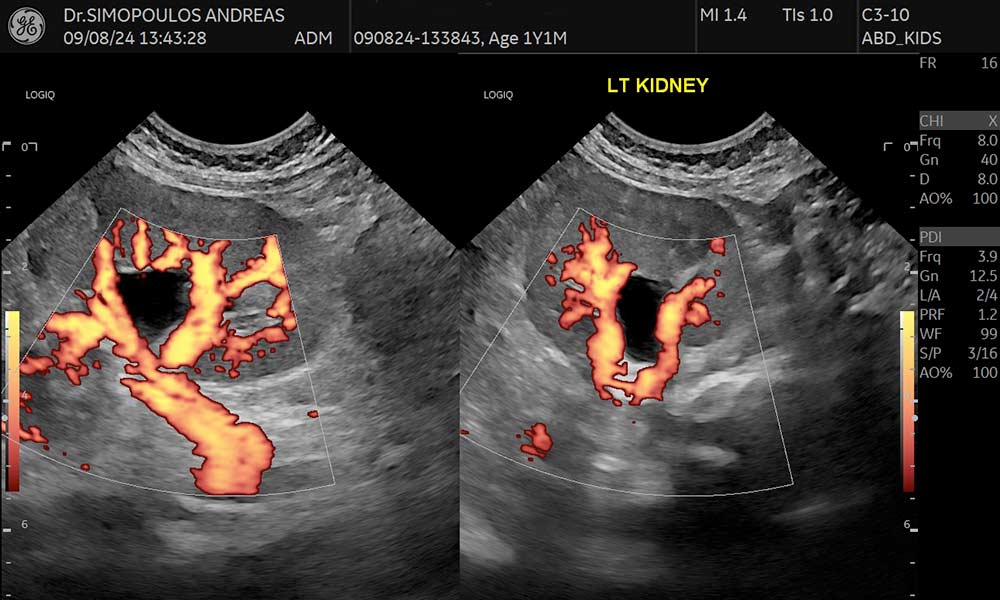

Εκτός από τις κλασικές μεθόδους (Color Doppler και Power Doppler), υπάρχει η δυνατότητα για πιο αντικειμενική τεχνική ανίχνευση της μικροαγγείωσης – MVI (Microvascular Imaging), τεχνική B-Flow, σε περιοχές ιδιαίτερα χαμηλών αιμοδυναμικών ροών καθώς και η νέα τεχνολογία Radiant Flow (Εξελιγμένη απεικόνιση έγχρωμου Doppler η οποία προσφέρει πληροφορία βάθους για την καλύτερη οριοθέτηση των αγγείων προσδίδοντας την αίσθηση της 3D απεικόνισης).